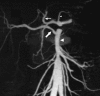

The arterial and venous circulation of the bowel is complex and is characterized by marked redundancy of multiple interconnecting branches, which provides a rich blood supply to aid in the digestive process and also serves to protect the bowel from potential ischemia or infarction. As a result of this circulatory pattern, anatomic variants and extensive collateral pathways are common. A thorough knowledge of both the arterial and venous mesenteric circulation, including normal, variant, and collateral anatomy, is necessary for the appropriate evaluation and management of the various disease processes that may affect the vascular supply of the gastrointestinal system.